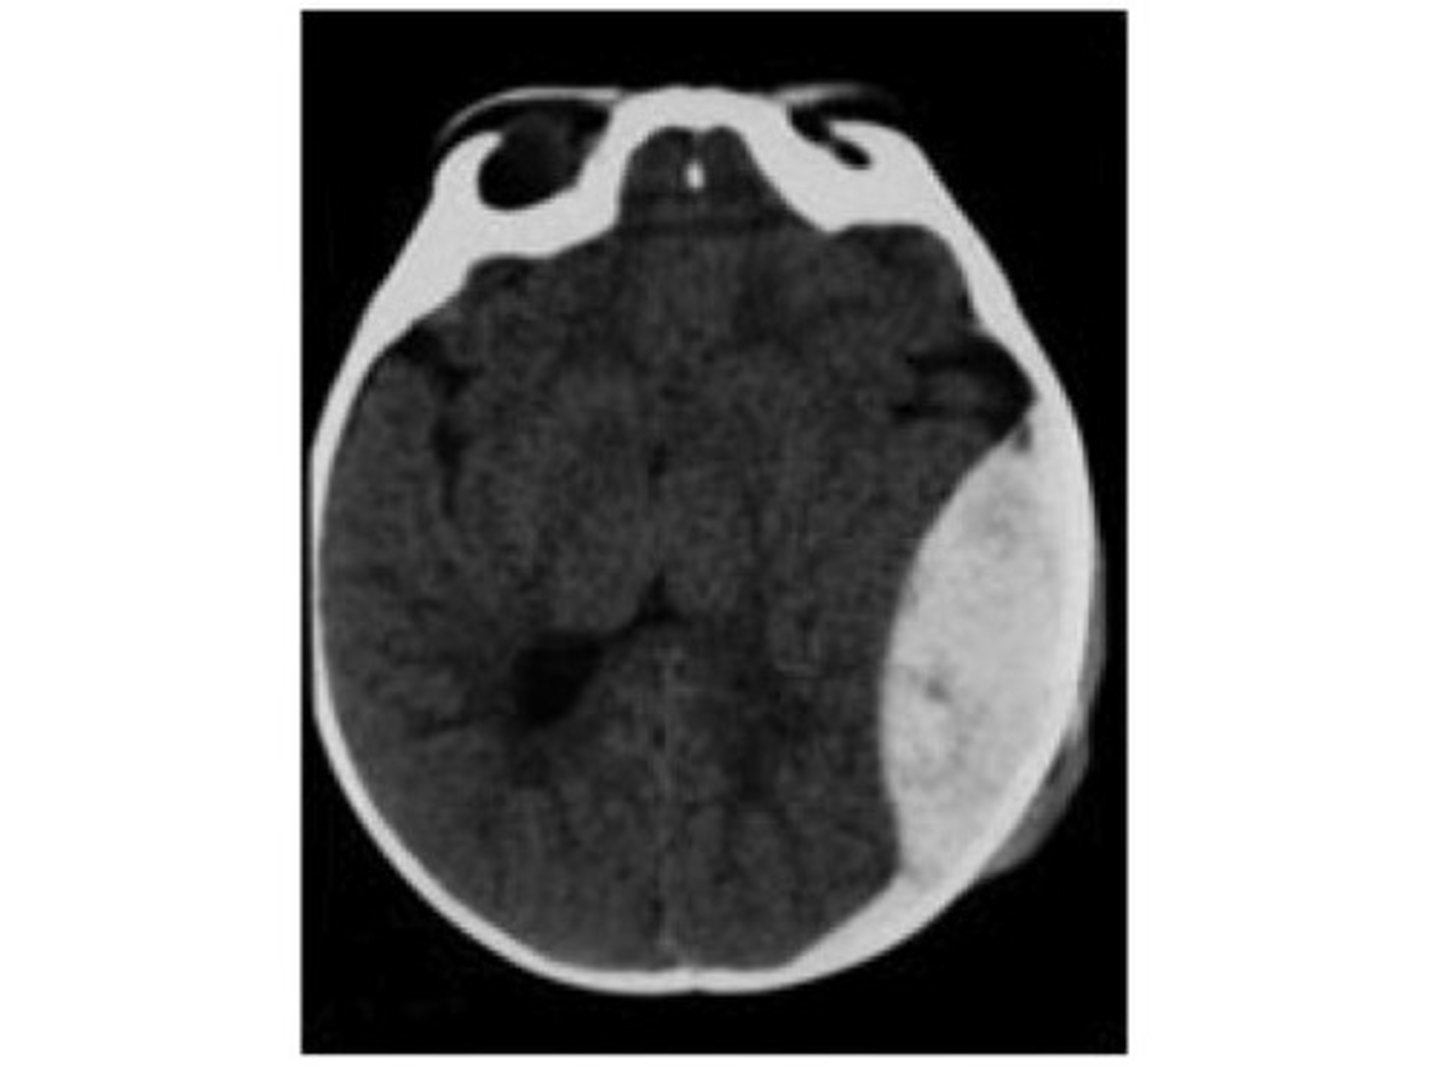

intracranial hemorrhage (ICH)

bleeding within the skull that leads to increased ICP and reduced cerebral perfusion

*traumatic or spontaneous

*major cause for neurologic morbidity and mortality

subdural hemorrhage

venous bleeding between the dura and arachnoid

*due to rupture of bridging veins

ICH

presentation of what impairment/issues with what cranial structure?

- headache

- nausea/vomiting

- altered consciousness

- weakness

- speech or vision deficits

- seizures

- rapid neurological decline